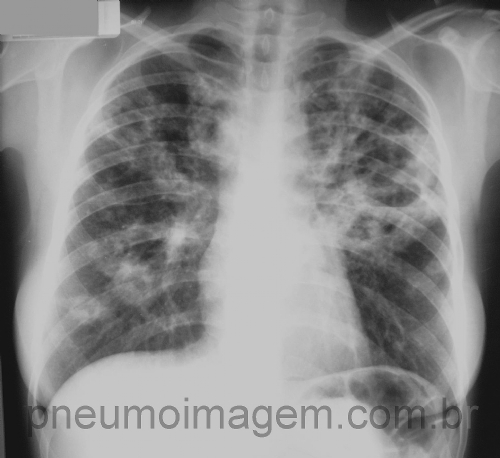

CASO CLÍNICO #33

CASO CLÍNICO #33Nem tudo é o que parece ser. Muitas vezes a tuberculose não aparece sozinha e, sim, associada a outras doenças, como neste caso. Qual a sua hipótese para a imagem? Deixe os seus comentários abaixo.

Not everything is what seems. Many times TB is not an isolated disease, but is associated with other diseases, as in this case. What is your hypothesis for the image? Write your comments below.